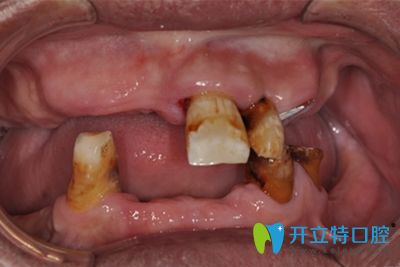

本院手術(shù)網(wǎng)友分享